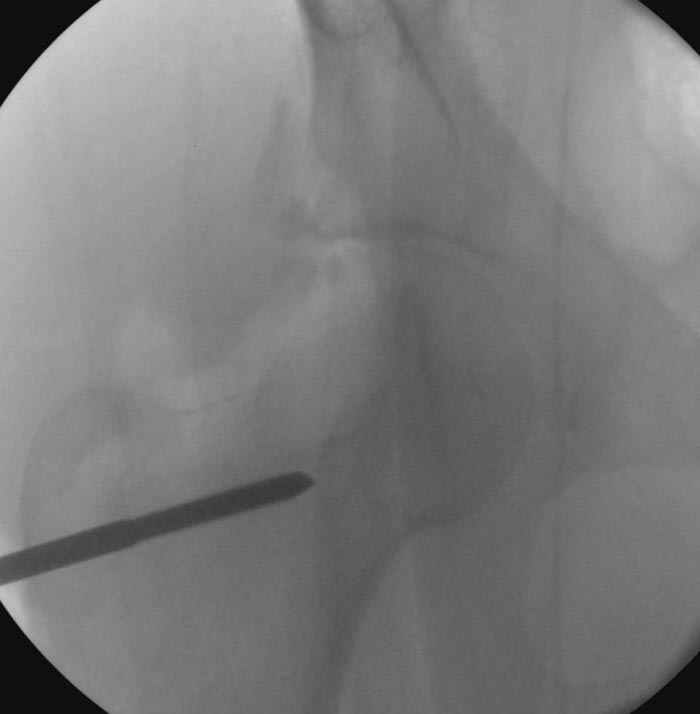

5:24 Рентгенограмма таза, вызывают врача ортопеда (снимок N1), его диагноз: закрытый переломо-вывих правого тазабедренного сустава, получает добро на закрытую репозицию в приемном отделении

5:38 Дважды неудачная попытка закрытой репозиции в приемном отделении

N 2

6:20 ответстенный врач принимает решение о репозиции в условиях операционной, предупреждаются родственники и больной, что при неудачной закрытой репозиции, о возможности открытой репозиции и фиксации задней стенки вертлужной впадины.

7:30 начало операции, больной на спине, попытка репозиции после анестезии N3, укладка больного на боку, доступ Kocher- Langenbeck, состояние седалищнего нерва около 2.5см кровоподтек, через joistick головка бедра приподнята, освобовождение сустава, фрагмент заднего края более 3х4 см репонирован на свое место. После промывания